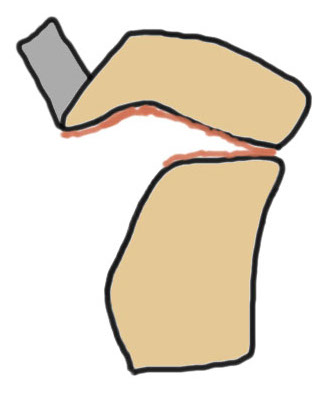

Ogden Classification

A: Undisplaced

B: Displaced

| Type I | Type II | Type III | Type IV |

|---|---|---|---|

| Avulsion distal tibial tubercle | Extension into tibial physis but not into knee joint | Extension across tibial physis and into knee joint | Extends posteriorly across tibial physis |

| Disrupts extensor mechanism | Disrupts extensor mechanism |

Disrupts extensor mechanism Disrupts articular surface Disrupts growth plate |

Disrupts extensor mechanism Disrupts articular surface Disrupts growth plate |

|

Associated Osgood-Schlatter Second most common |

Most common Risk of compartment syndrome |

Risk of compartment syndrome |

Type IB

Type IIB

Type III

Comminuted Type III